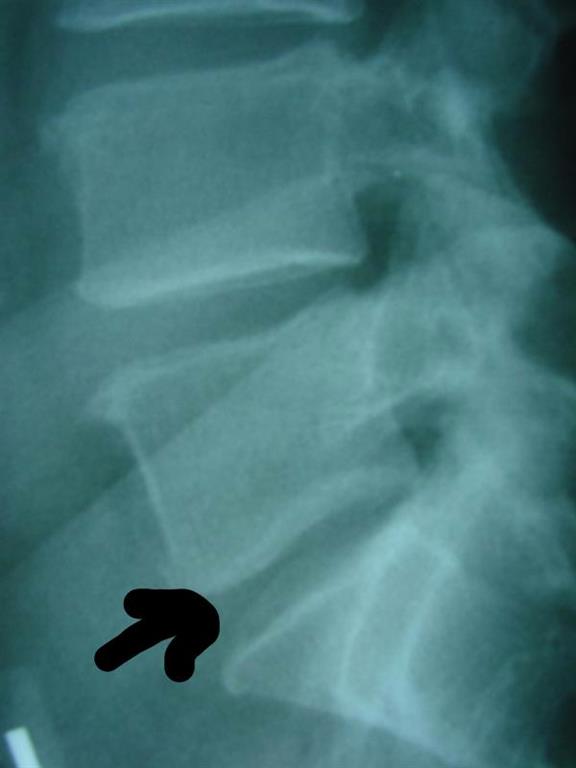

So when do you seek medical help? When you hurt! And what's the most common cause of pain in adults? Low back pain! It's the second condition that sends patients seeking care. In one study, the average age of low back pain care hospitalizations was 47.8 years with only 3.1% of those patients having a surgical procedure. (1) Luckily, that’s just lower percentage of patients, leaving 97% of patients in need of non-operative care. Shoreline Medical Services/ Hutter Chiropractic Office offers Groton chiropractic care that is non-operative and relieving for Groton back pain.

Patients with leg pain, weakness and paresthesias due to lumbar spine disc herniations do well and improve with non-operative care. Researchers write thatback surgery as an intervention is reserved for those patients who have severe or progressive motor deficit or symptomatology of bowel or bladder control loss. (3) So that's where your Groton chiropractor comes into play! Chiropractic's strength is non-surgical care for those suffering with back pain and related leg pain radiculopathy, and Shoreline Medical Services/ Hutter Chiropractic Office’s forte is relieving non-operative care of Groton back pain and neck pain.

Sick discs - protruded discs, extruded discs, degenerated discs - show lower levels of glycosaminoglycan (GAG) content. And these discs will show this loss biochemically before they show it on imaging. (5) So what is GAG? It's the building block of white fibrocartilage of the disc, essential for a healthy disc. It attracts fluid into the disc to keep it healthy and able to do its job. Do you know how healthy your discs are? If you have back pain, your discs are likely missing GAG. Let's talk at your next Groton chiropractic visit about how to improve those GAG levels with spinal nutrition.